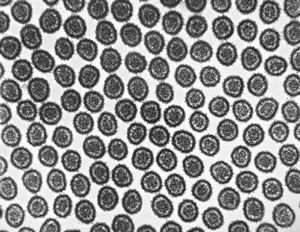

chylomicrons … negative staining